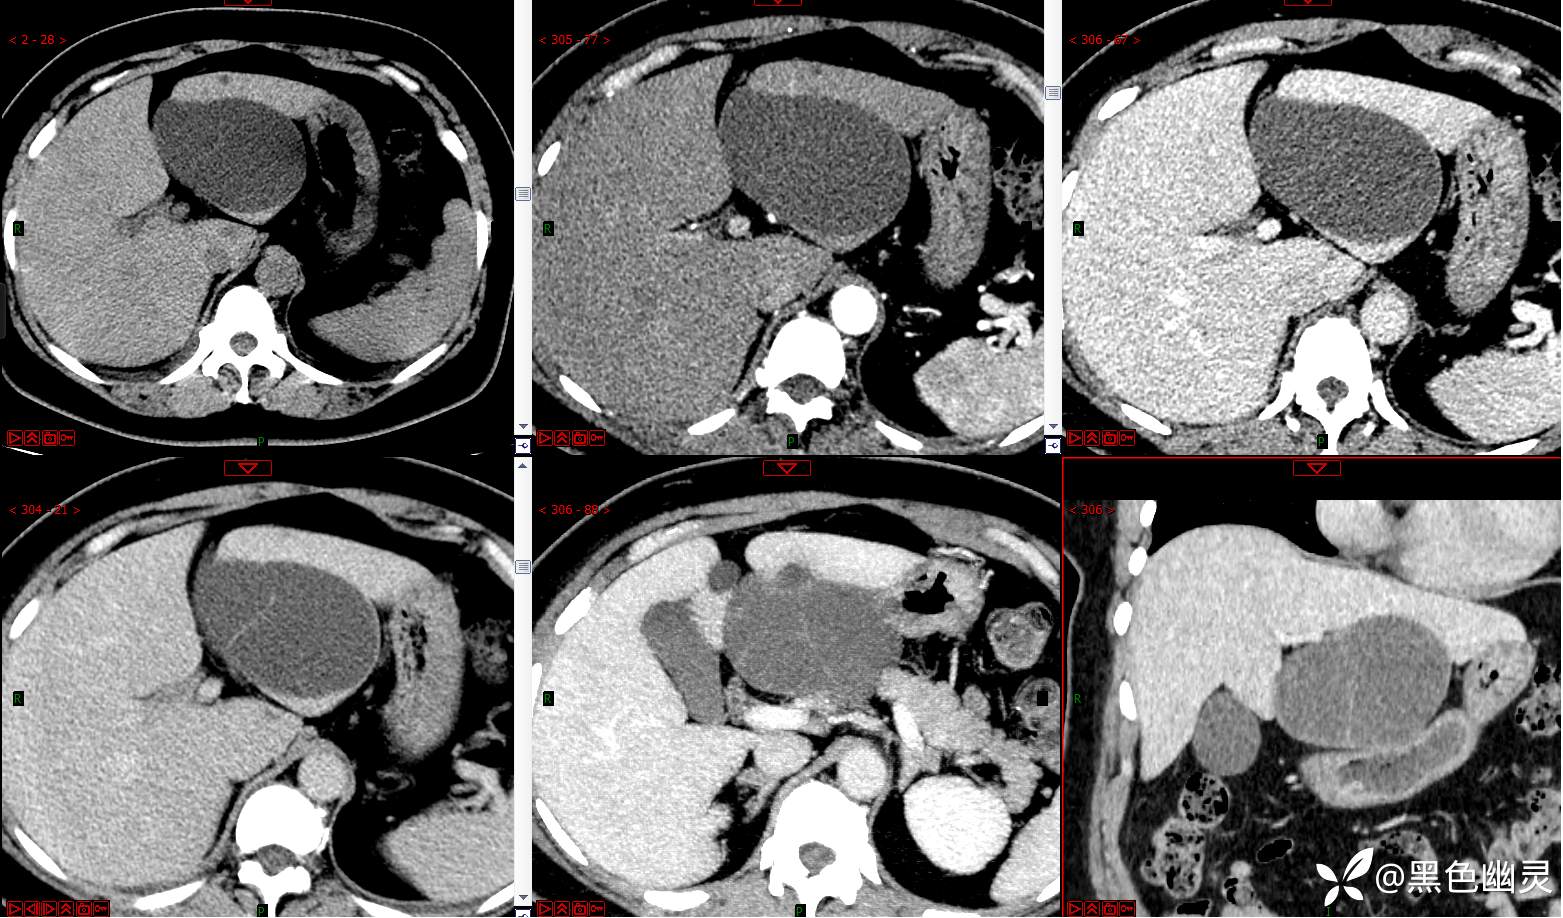

病例|肝脏占位,有病理。

患者,女,51岁,患者于3日前在我院体检行全腹部CT检查见肝脏多发囊肿,病程中患者无不适症状,未行治疗。现为进一步手术治疗入我院门诊,我科拟行“肝囊肿”收入院。病程中无咳嗽,咳痰,胸闷,气喘,头晕等不适,发病以来食量尚可,二便未见异常,体重无明显增减。